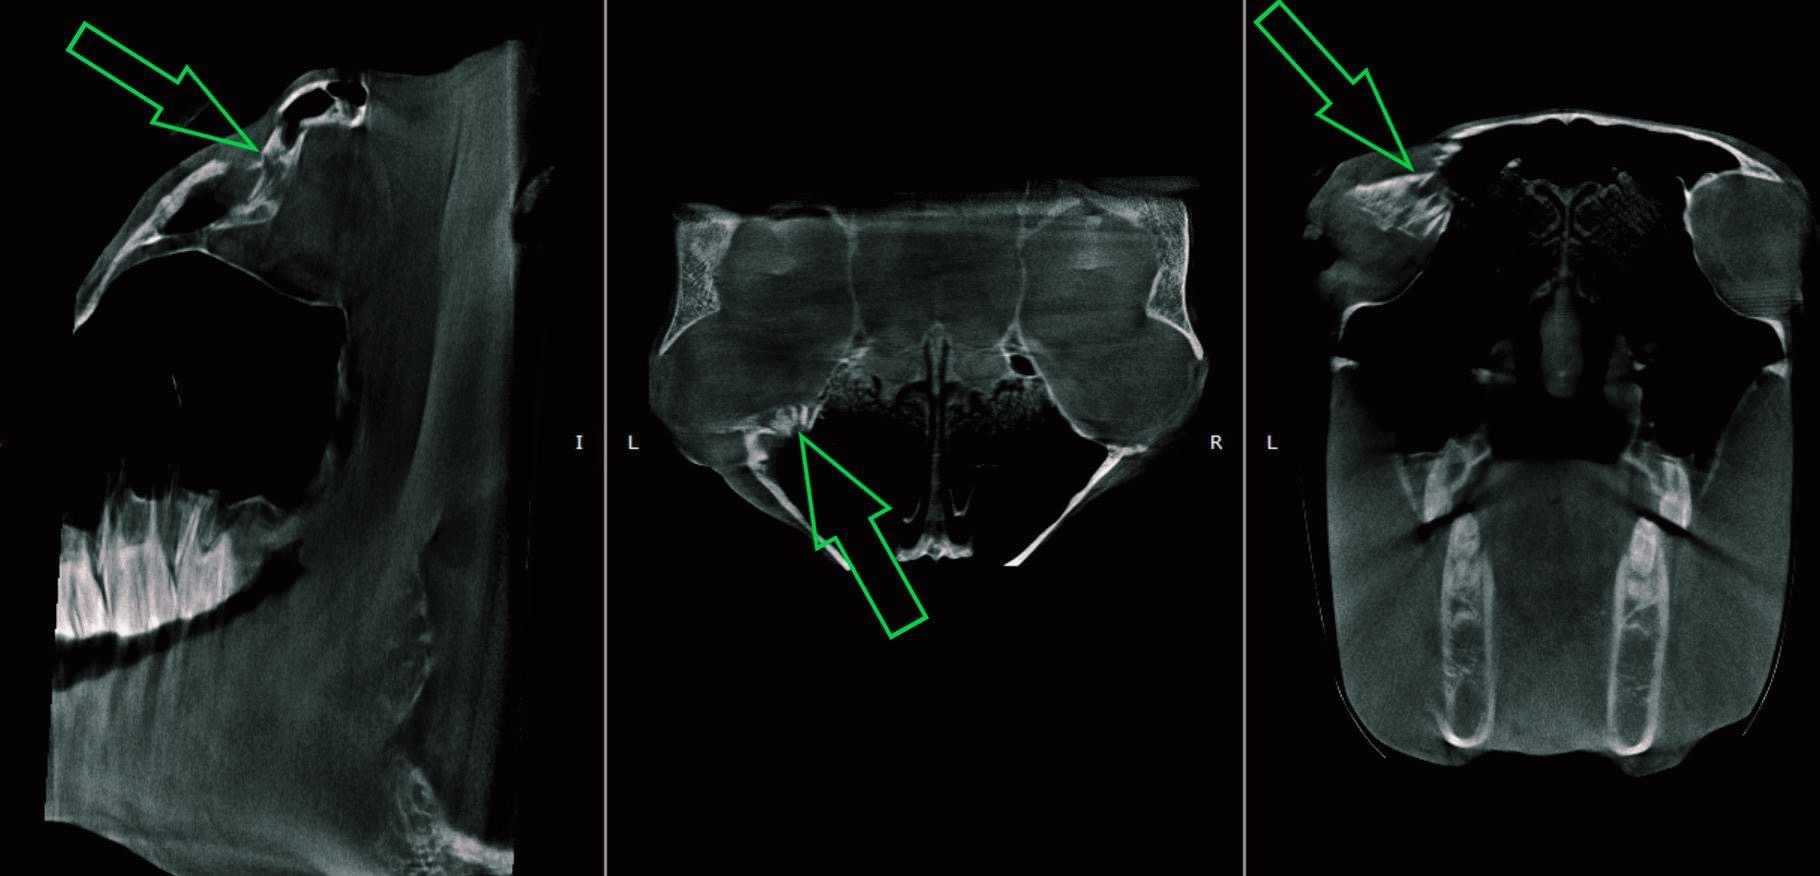

He had suffered a kick to the face and when he came out for a lesson or supplements he presented with a shifted eye position. Upon further vet testing he was CT scanned and they identified an orbital fracture from the kick causing the shift in the eye. He still had full vision and use of the eye, but he now had a larger eye corner for debris, flies etc. Down below are the photos from Steinbeck during the process.